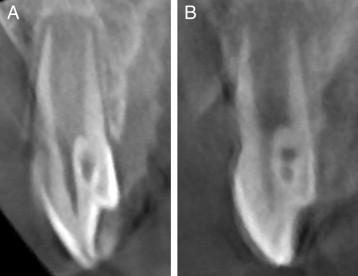

What can we see on the tooth in figure A?

Dens evaginatus

What’s happening with the tooth in the marked area?

Dens invaginatus